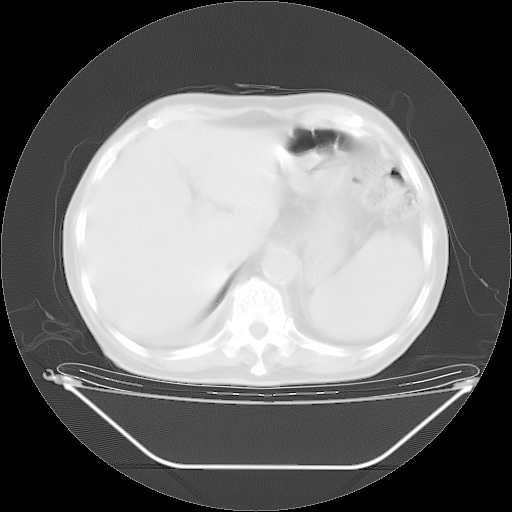

胸腹部CT,诊断意见:左上肺叶钙化灶、左侧胸膜局限性增厚并钙化、胆囊炎。描述部分肺组织呈磨玻璃样改变。